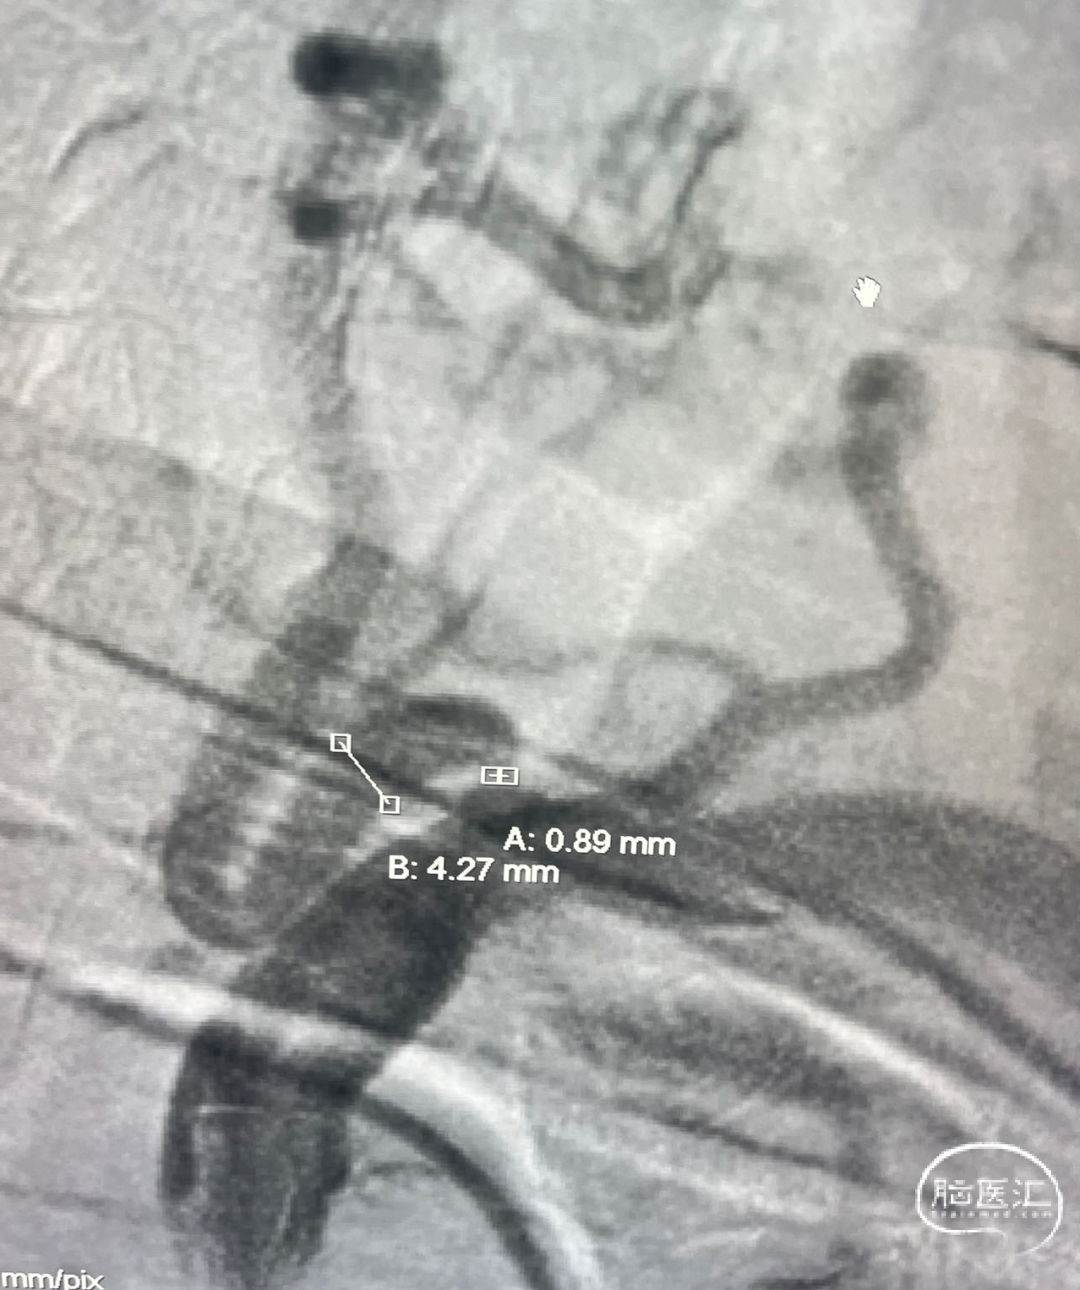

测量病变:

远端4.27mm、狭窄处0.89mm,狭窄程度约75%。